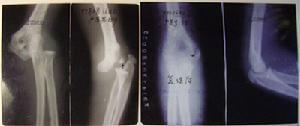

1.治療骨傷:傳統手法復位配合輕便穩妥的外固定,外敷久負盛名的梁氏接骨膏,藥分三期施治(內服中藥或中成藥),適時適度的功能鍛鍊,後期配合中藥燙洗等,一套完整有序的純中醫治療方法,不開刀,不住院,無創傷,傷痛小,花錢少,骨折癒合快,功能恢復快,所長梁振興在全面繼承的基礎上大膽創新,研創了多種行之有效的治傷新技術新方法,把梁氏正骨術發展到了一個新的頂峰,提高了對疑難病症的診斷符合率和治癒率,大大縮短了療程,所治骨折無不癒合者。

經典案例